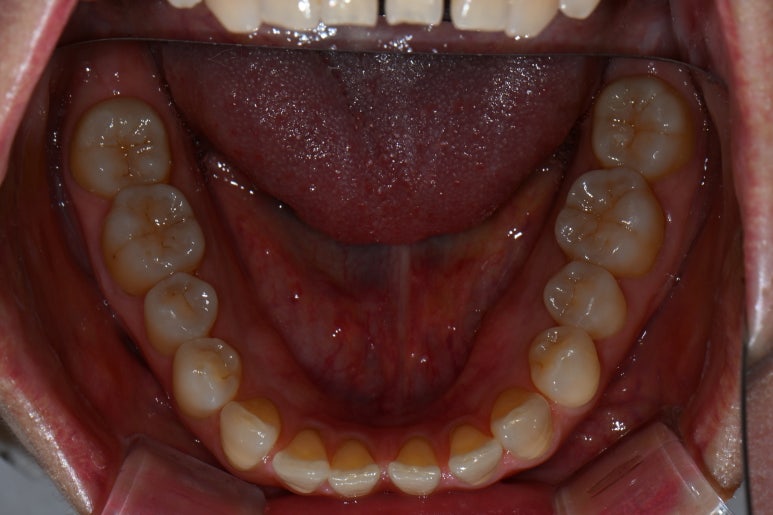

씹는 면에서 보시면 더욱 문제점이 잘 보입니다.

앞니 사이에 공간도 많으시고... 기존의 레진은 하염없이 두껍게만 붙여나가고 있는 수순이고..

앞니 벌어짐 + 레진 변색은 정말로 라미네이트 치료를 받기에 가장 적합한 경우라고 생각합니다.

그리고 하나 더 ! 이 분의 경우 아래 앞니에도 치아 사이 공간이 있어 많이 벌어짐이 있었는데요,

옛날부터 어르신들이 치아가 벌어져 있으면 복이 새어나간다고 하시잖아요~ 레진으로 양 옆에 붙여서 메꿔주는 것도 방법이지만, 얇은 세라믹을 붙여서 앞으로 변색 없이 완벽한 모양과 색상으로 유지해나가실 수 있을겁니다.

아래 앞니도 교합면에서 보면 생각보다 치아 사이 벌어짐이 많이 있으신 것을 보실 수 있을겁니다.